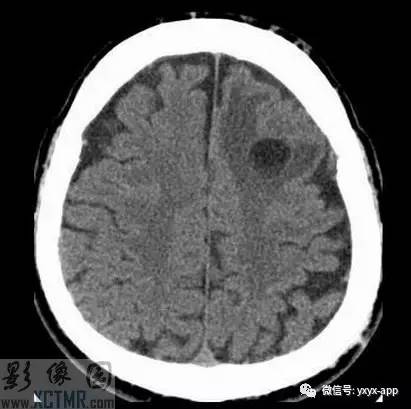

CT:左侧额叶一囊性肿块伴水肿。MRI:轴位T1WI和T2WI显示左侧额叶一囊性肿块伴周围脑实质显著水肿,但无明显占位效应。T1WI增强图显示病变为分叶环形囊状肿块伴周围脑实质水肿,囊壁环形强化,囊内及周围水肿区无强化。

影像学表现取决于感染的位置以及感染的阶段。此病例在胶状水泡阶段,寄生虫的死亡引起明显的炎性反应。影像学表现包括:围绕囊性病变的血管源性水肿;增强后环状增强;T1WI胶状囊性病变周围为低信号;有时可见T1WI头节高信号影。